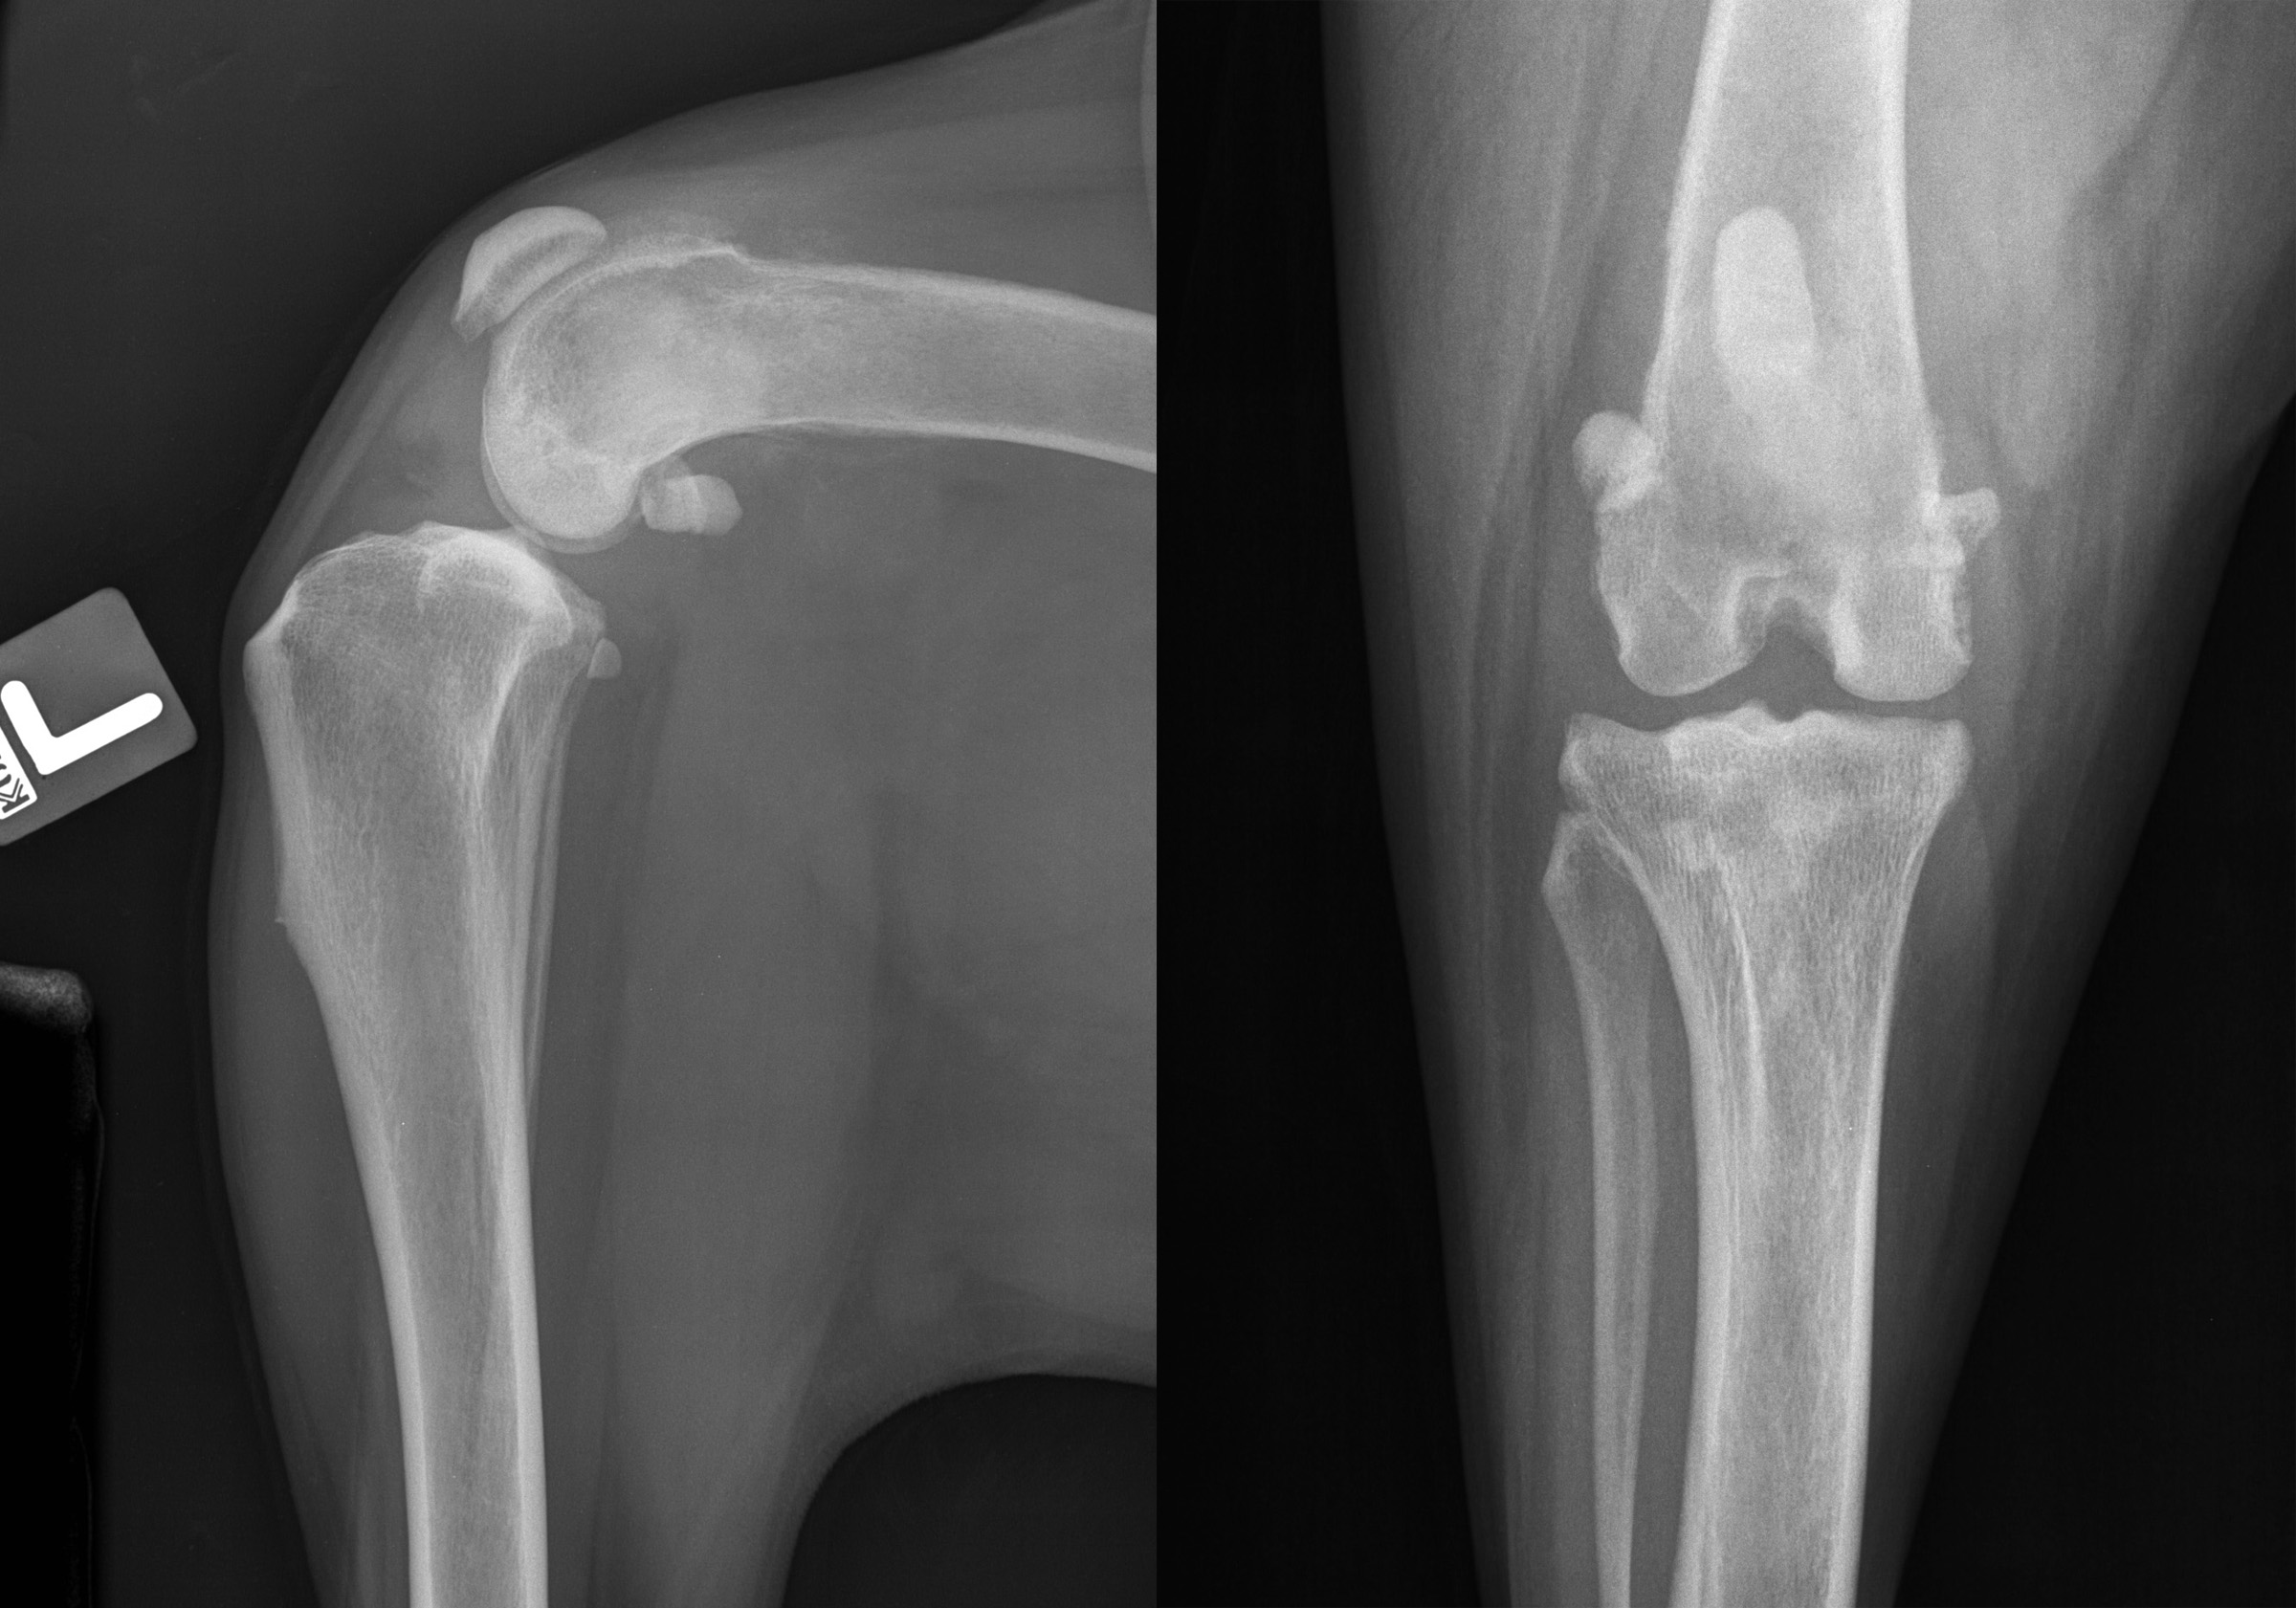

RadioQuiz 3: Docteur, mon chien boite…

Signalement: labrador, femelle opérée de 8 ans

Histoire Clinique: boiterie progressive au membre pelvien gauche.